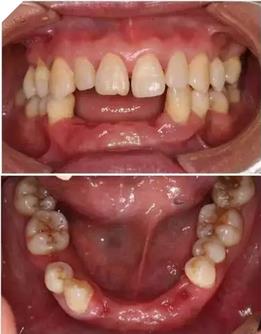

初診時(shí)下前牙不良修復(fù)體

利用3shape導(dǎo)板軟件虛擬排牙

以修復(fù)為導(dǎo)向規(guī)劃植體